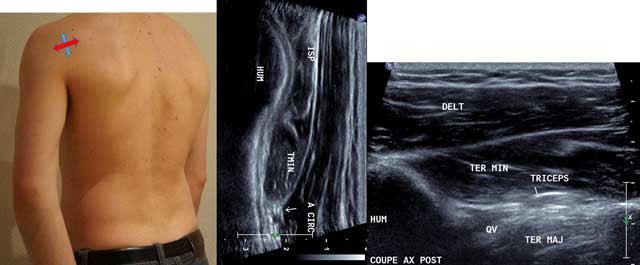

Intermediate axial cross section performed in the axis of the long head of the Triceps Brachii covering the Teres Major muscle (in abduction / internal rotation similar to the infraspinatus exploration) (Figure 3).

Figure 3

Sagittal oblique view (blue arrow) and axial intermediate view (red arrow) with HUM: Humerus, ISP: Infraspinatus, TMIN: Teres minor, A CIRC: Axillar Artery, DELT: Deltoid Muscle, TER MAJ: Teres Major, QV: Velpeau space, Triceps: Tricipal Muscle.